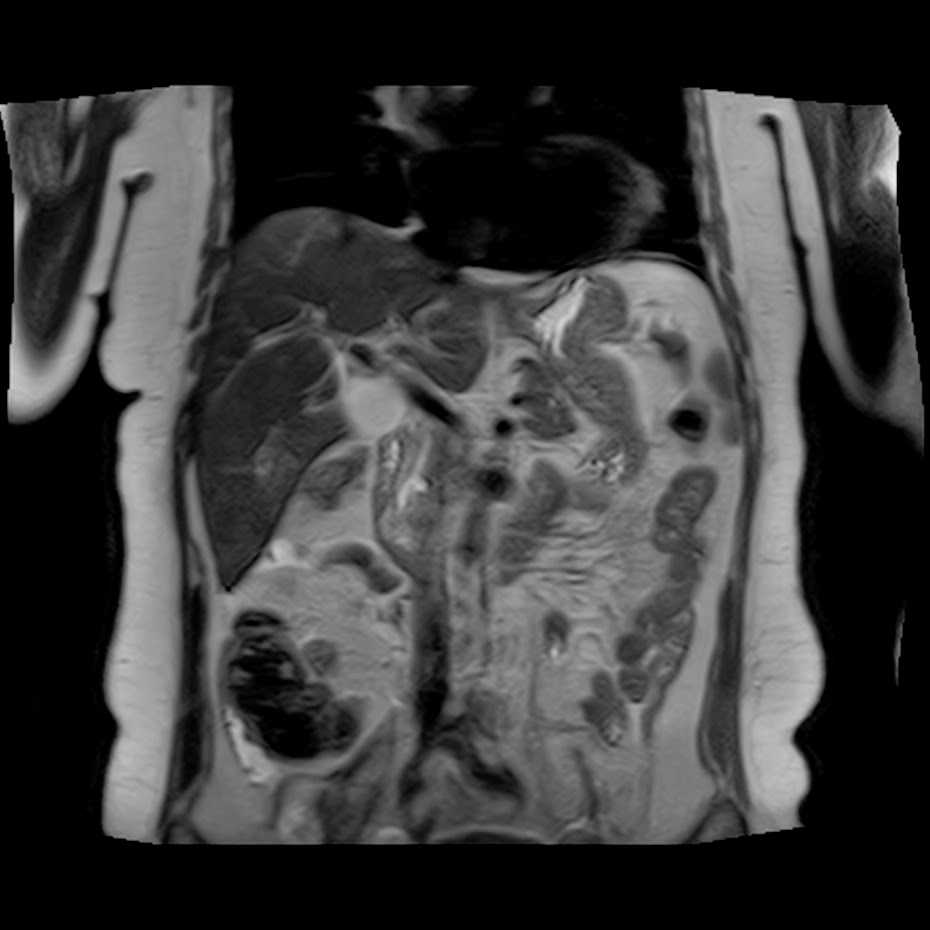

Caso interesante #5

Paciente con dolor en hipocondrio derecho.